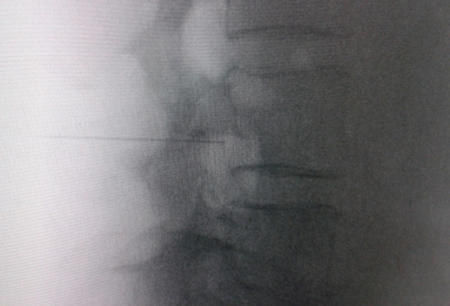

El acceso por vía transforaminal es el más utilizado (4). Se coloca al paciente en decúbito prono con una almohada a nivel abdominal para revertir la lordosis fisiológica. Las agujas o cánulas de radiofrecuencia que utilizamos con más frecuencia son de diámetro 20 o 22 G de 98 mm de largo con punta activa de 0,5 o 1 cm. Después de la asepsia con clorhexidina alcohólica y la colocación de campos estériles, se realizan enfoques radiológicos en incidencia anteroposterior, oblicuo y lateral. En incidencia anteroposterior y moviendo el arco en dirección cráneo caudal se borra el doble arco del borde inferior vertebral. En incidencia oblicua entre 20 y 30 grados ipsilateral al GRD a tratar, se visualizará la clásica imagen descrita como de “Scotty Dog”, que es resultado de acercar el macizo facetario y la apófisis espinosa al lado contralateral. El punto de entrada será entonces inmediatamente debajo del pedículo. Previa anestesia local con lidocaína al 1 %, la aguja se introducirá siguiendo una visión túnel y no se avanzará más allá de la mitad del pedículo en esta proyección con la finalidad de prevenir la lesión neural. En proyección lateral, se introducirá en el techo del neuroforamen

(Figuras 1 y 2) pero la localización final será determinada por la estimulación nerviosa sensitivo-motora. La estimulación sensitiva consiste en provocar parestesia o dolor en el territorio afectado con una estimulación entre 0,3-0,6 v. Durante la estimulación motora se pueden provocar fasciculaciones en el territorio afectado con un voltaje del doble al necesario para provocar las parestesias. Si se desea realizar una denervación intraganglionar, promulgada por algunos autores, la estimulación tanto sensorial como motora será positiva a menos de 0,3 v. Por tratarse de un procedimiento más doloroso, se aconseja administrar anestésicos locales después del estímulo doloroso y antes de realizar el tratamiento. La impedancia deberá mantenerse por debajo de 450 ohms, lo que se consigue infundiendo solución salina previa a la RF (4). La utilización de contraste constituye una buena práctica, ya que descarta la posición intravascular e intratecal de la cánula de radiofrecuencia.

Fig. 2. Imagen radiológica anteroposterior de una cánula de radiofrecuencia posicionada en neuroforamen L4-L5, en el llamado triángulo de seguridad, después de la inyección de contraste. Se observa un engrosamiento del radiculograma a nivel del techo del neuroforamen, que podría corresponder al ganglio de la raíz dorsal de L4